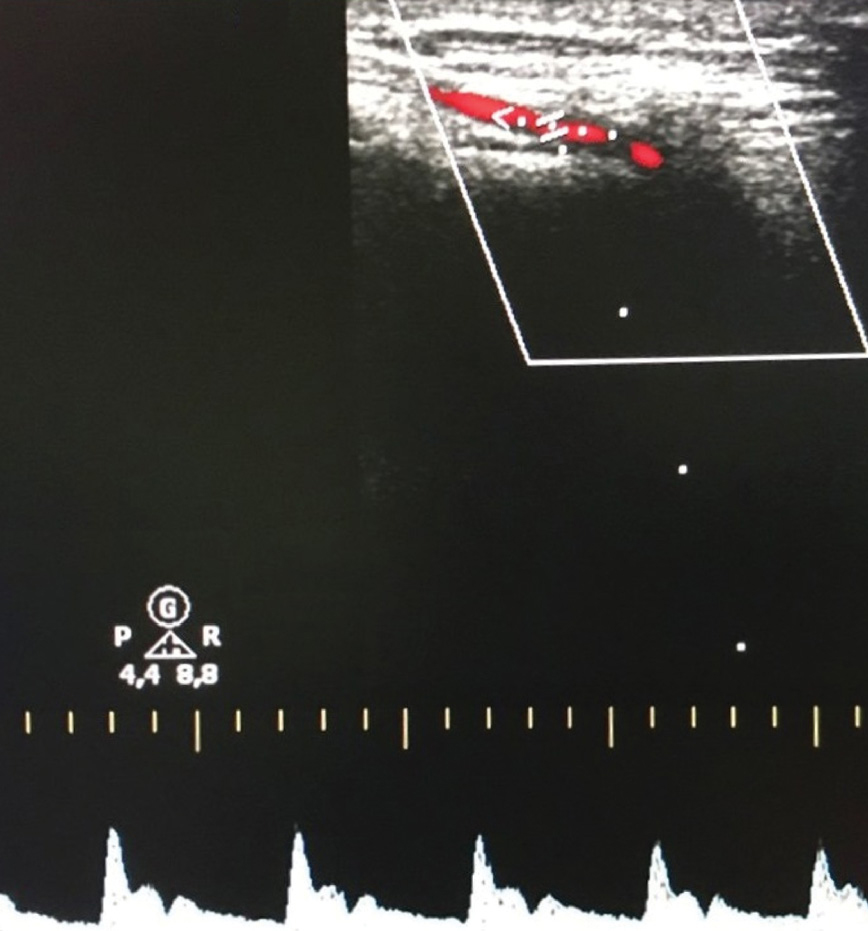

На ОПТГ наблюдается 30 постоянных зубов, отсутствуют зубы 3.8, 4.8. (рисунок 3). Анализ телерентгенограммы головы в боковой проекции (ТРГ) в программе Dolphin Imaging (США) (рисунок 4) показал: нормальные значения угла SNА = 81,2° (норма = 82°±2) и длины основания верхней челюсти (ANS-PNS) = 49,7 мм (норма = 51,6 мм); увеличение угла SNB = 87,1° (норма = 80°±2) и длины основания нижней челюсти (Pg-Go) = 85,7 мм (норма = 74,3 мм); отклонение и отрицательное значение угла ANB = -6 ° (норма = 1±1°); Wits-число равное -8.7 (в норме 1±1), что подтверждает наличие скелетной формы мезиальной окклюзии, обусловленной передним положением и макрогнатией нижней челюсти при нормогнатии и правильном положении верхней челюсти относительно переднего отрезка черепа. Это позволяет предположить наличие изменений в сосудах головы и шеи и гемодинамики в них. Для подтверждения диагноза была проведена ультразвуковая допплерография (триплексное сканирование) сосудов головы и шеи справа и слева (рисунок 5).

Рисунок 5. УЗДГ поверхностной височной артерии пациентки Т., 18 лет, с мезиальной окклюзией гнатической формы до операции на нижней челюсти.

Было выявлено усиление максимальной систолической скорости в лицевой и задней ушной и поверхностно височной артериях. Диастолическая скорость кровотока выше нормы в НСА, поверхностной височной и задней ушной артериях. Имеется асимметрия, изменение кровотока более выражено слева. Индекс Пурсело (показатель периферического сопротивления кровотока) выше среднестатистической нормы (0.7) в НСА, лицевой, поверхностной височной и задней ушной артериях. Также обнаружены гемодинамически незначимое изменение линейного хода позвоночных артерий с двух сторон.

Совместное использование приведенных методов позволило сделать заключение и поставить окончательный диагноз пациентке Т., 18 лет: мезиальная окклюзия (гнатическая форма), эхографические признаки гемодинамически значимых нарушений в бассейне НСА, а также ее мелких ветвей – лицевой, поверхностной височной, задней ушной артериях.